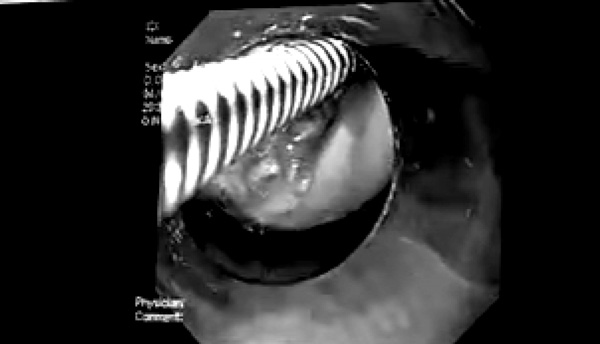

Chị T. được đưa vào bệnh viện cấp cứu, ngay lập tức được các bác sĩ thăm khám hội chẩn kíp nội soi tiêu hóa, phát hiện một dị vật nằm trong đường thực quản đoạn 1/3 trên thực quản của bệnh nhân. Kíp nội soi cấp cứu đã tiến hành gắp ra một túi mật lợn tươi, kích thước khoảng 3cmx4cm.